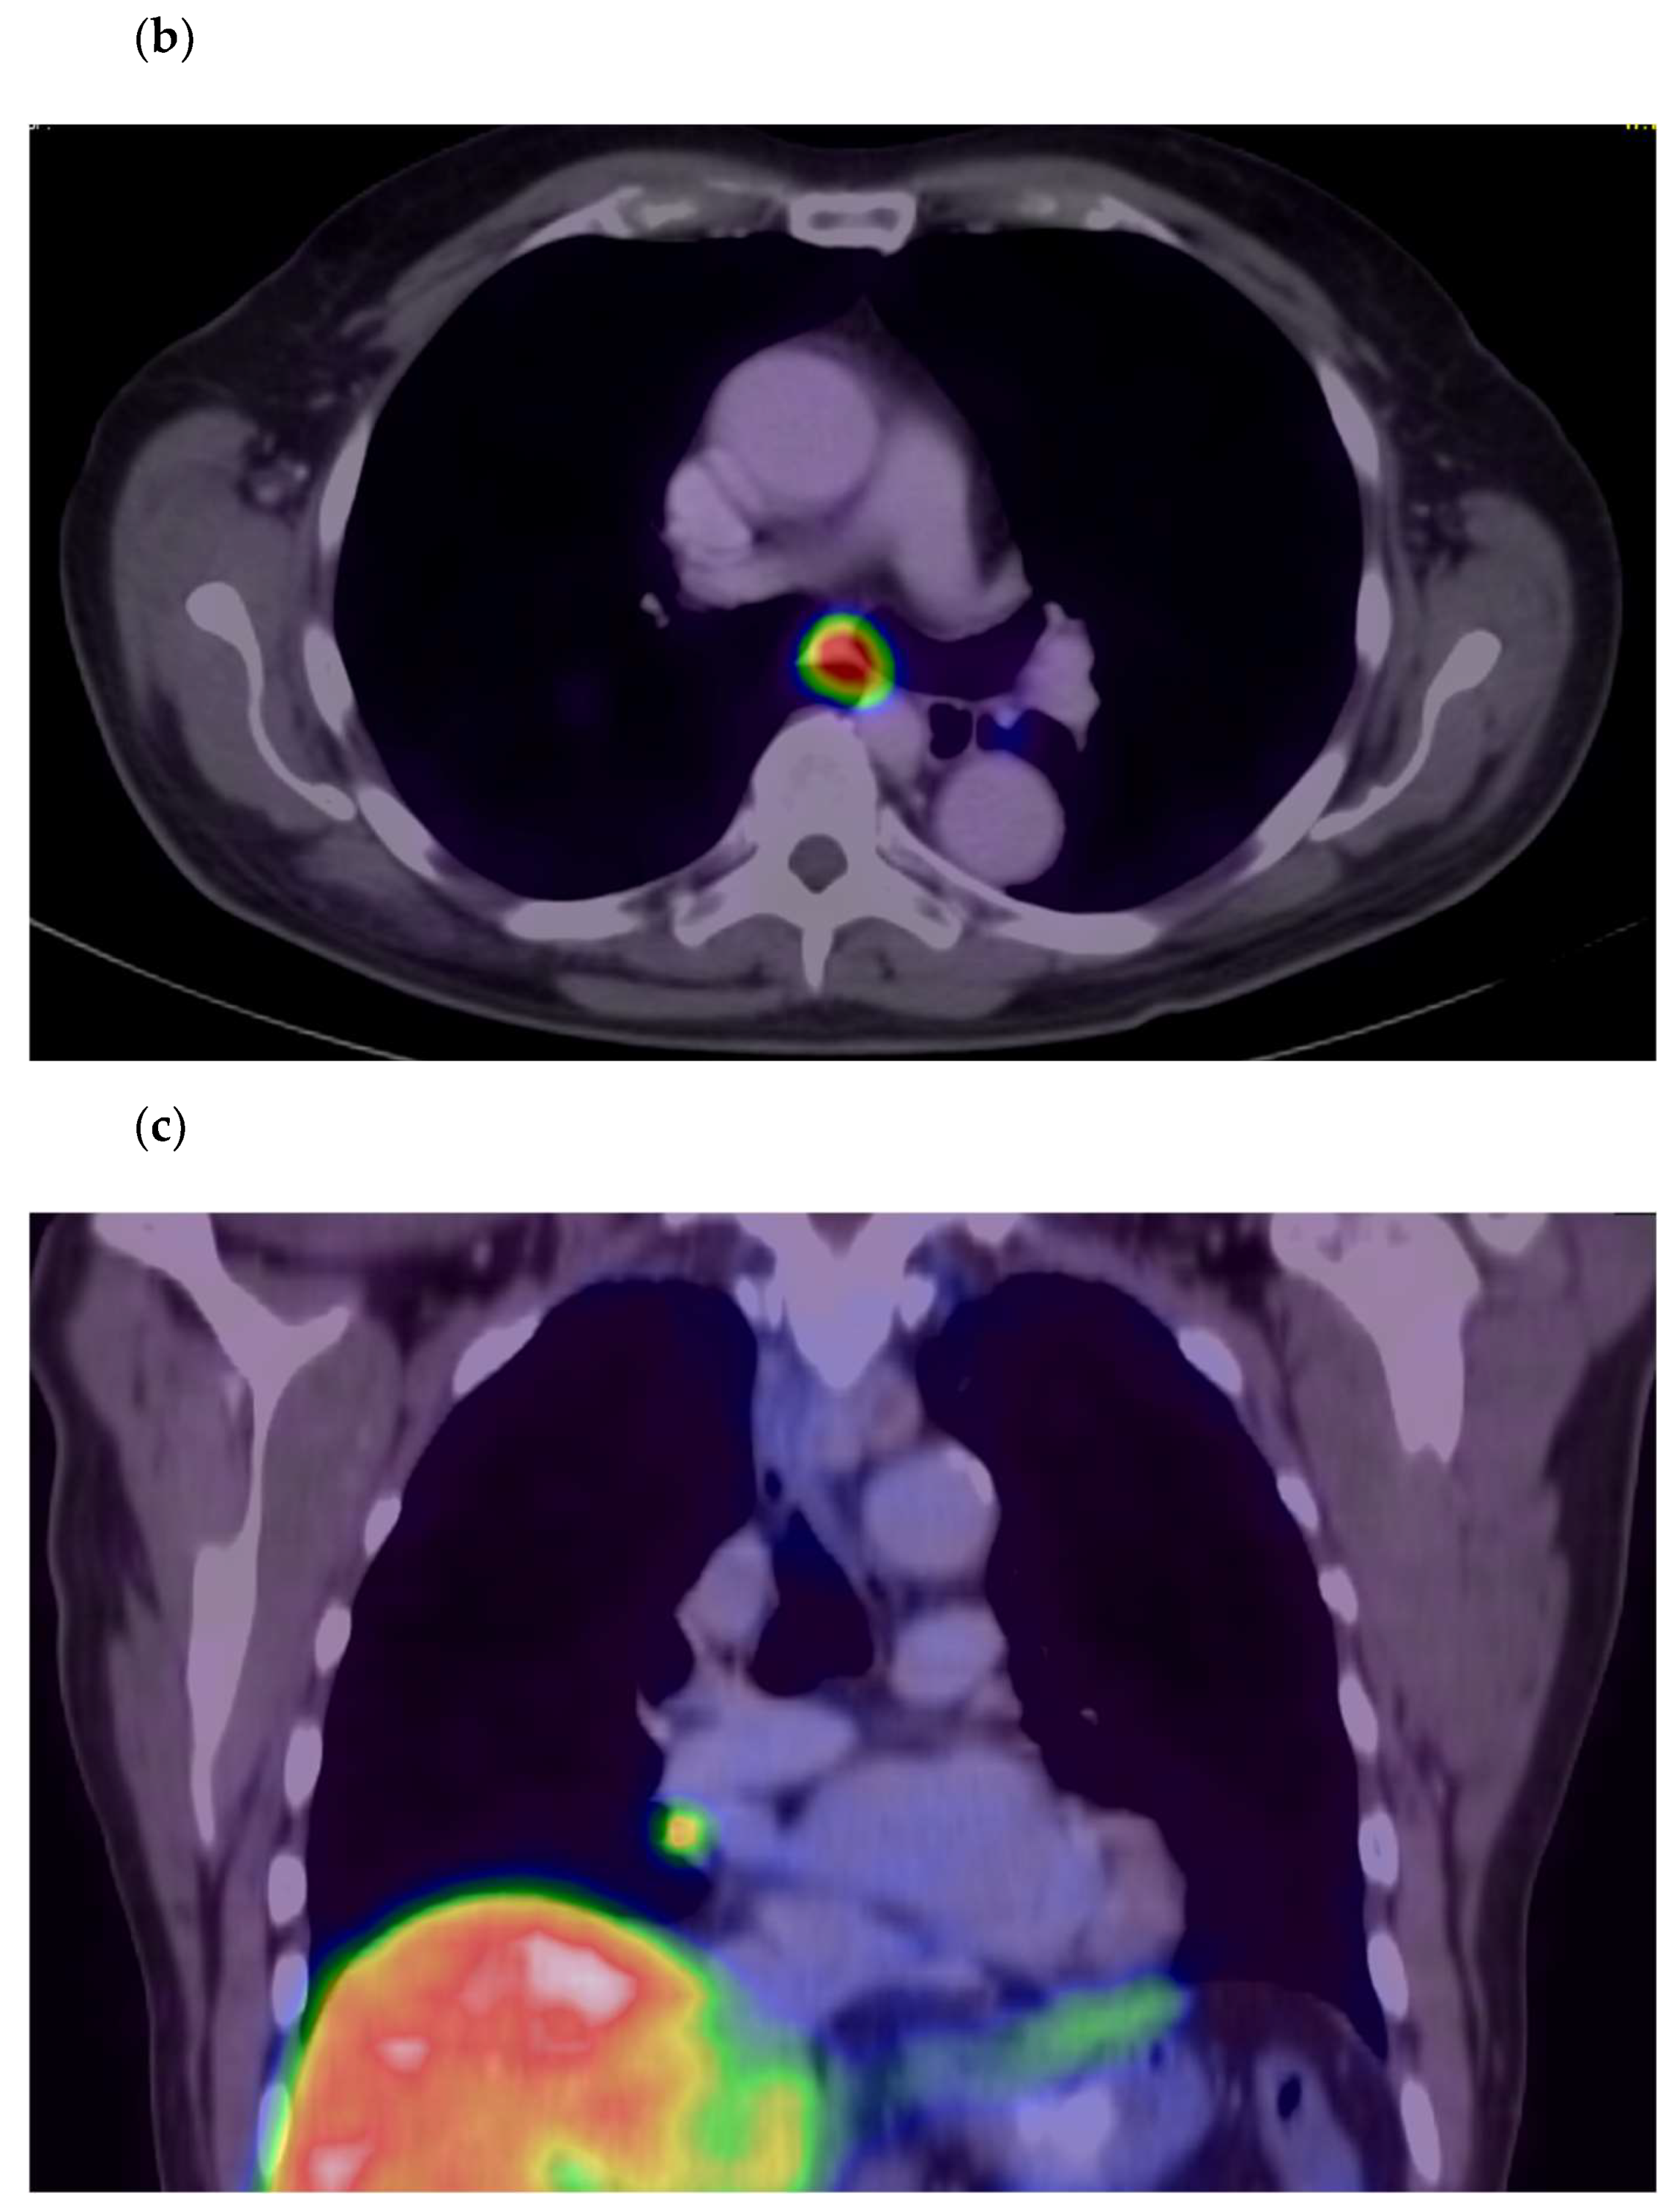

3. Results